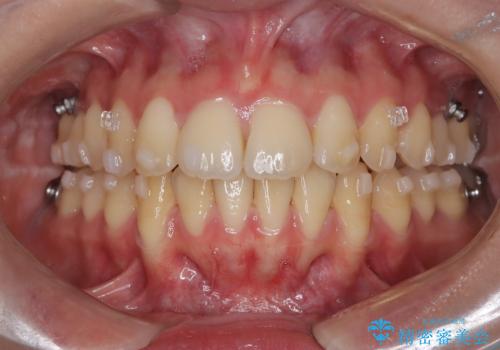

- 矯正装置

- インビザライン

- 前歯の突出を主訴に来院されました。

アンカースクリューとインビザラインを用いて遠心移動を行うことでできる限り前歯を下げて叢生の改善を行いました。